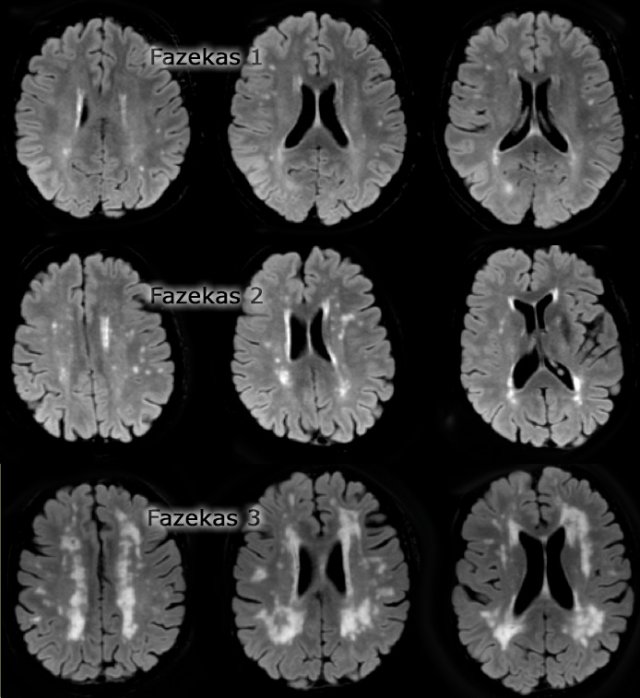

Fazekas scale for WM lesions

On MR, white matter hyperintensities (WMH) and lacunes - both of which are frequently observed in the elderly - are generally viewed as evidence of small vessel disease.

The Fazekas-scale provides an overall impression of the presence of WMH in the entire brain.

It is best scored on transverse FLAIR or T2-weighted images.

Score:

- Fazekas 0: None or a single punctate WMH lesion

- Fazekas 1: Multiple punctate lesions

- Fazekas 2: Beginning confluency of lesions (bridging)

- Fazekas 3: Large confluent lesions

Fazekas 1 is considered normal in the elderly.

Fazekas 2 and 3 are pathologic, but may be seen in normally functioning individuals.

They are however, at high risk for disability.

In 600 normally functioning elderly people the Fazekas score predicted disability within one year (table).

In the Fazekas 3 group 25% was disabled within one year (10).

Three year follow-up shows that severe white matter changes independently and strongly predict rapid global functional decline (17).

A limited amount of white matter hyperintensities may also occur in the normally ageing brain (Fazekas grade 1).